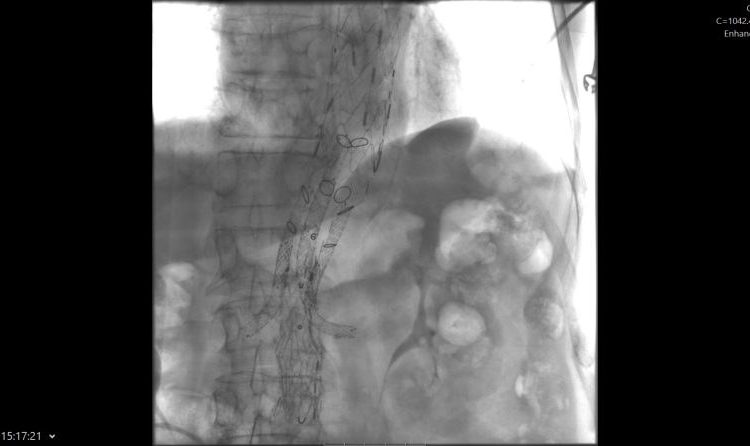

„Ovakvi zahvati predstavljaju vrhunac suvremene endovaskularne medicine i zahtijevaju iznimnu koordinaciju multidisciplinarnog tima koji uključuje interventne radiologe, kardiokirurge, vaskularne kirurge, anesteziologe, inženjere radiologije, instrumentarke i anestezičare. Tijekom zahvata ugrađena su ukupno tri stenta duž aorte, od arterije subklavije do bifurkacije aorte. Kako bi se osigurala adekvatna prokrvljenost vitalnih organa, postavljen je posebno dizajniran stent s otvorima za bubrežne arterije te arterije koje opskrbljuju crijeva“, pojasnio je dr. Gojko Bogdan, voditelj Kliničkog odjela za vaskularnu i intervencijsku radiologiju te dodao se pacijent nakon zahvata osjeća odlično.